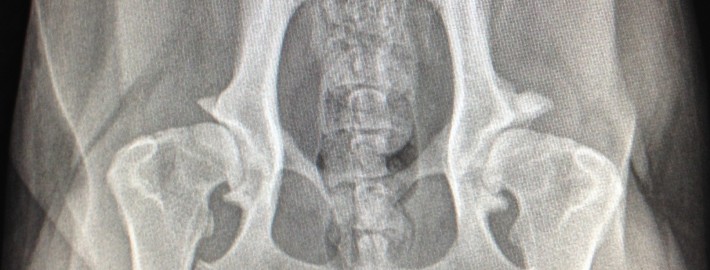

Voici ici des hanches normales. Les têtes fémorales sont bien rondes et entrées profondément dans l’articulation. L’espace articulaire est bien égal indiquant une bonne congruence. Les rebords osseux sont lisses, indiquant l’absence d’ostéoarthrose.